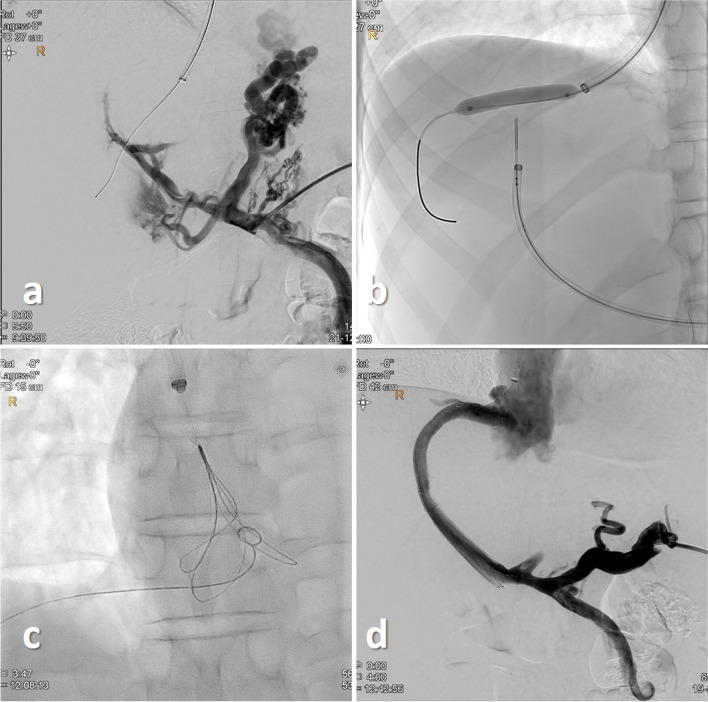

Background: Three patients with portal hypertension and gastrointestinal bleeding due to non-cirrhotic portal vein thrombosis were treated with portal venous recanalization transjugular intrahepatic portosystemic shunt (PVR-TIPS) via a trans-splenic access.

Main body: A "bottoms-up" retrograde puncture of the right hepatic vein was performed using a re-entry catheter to gain access to the right hepatic vein. In all patients a successful retrograde puncture of the right hepatic vein was achieved, thereby restoring the splenoportal tract.

Conclusion: Our cases present an alternative approach to treat chronic portal vein thrombosis expanding the possibilities of the PVR-TIPS procedure.